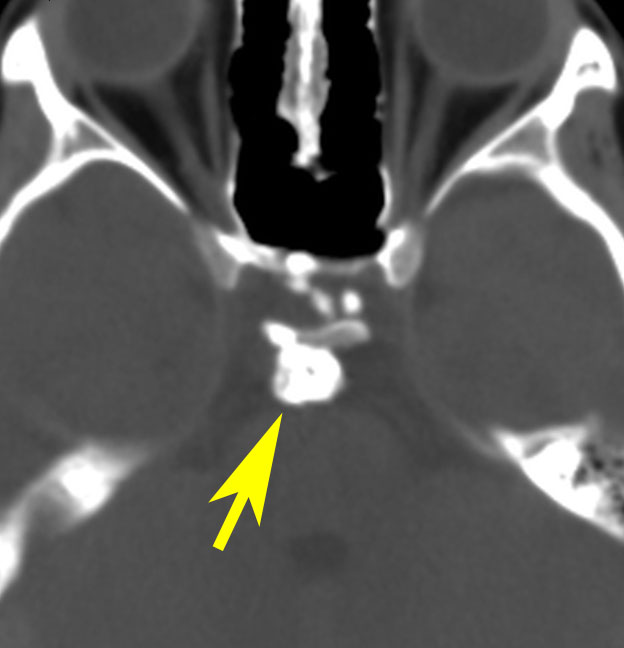

視神経への圧迫はとれたので,今度は腫瘍の本体を摘出しなければならないのですが,トルコ鞍上部に大きな骨化(黄色の矢印)があります。骨化は15mmくらいの大きさがありました。この大きな骨化は砕くことができずに,周囲を全部剥離して一塊にして引きずり出しました。後交通動脈の下側から引っ張りだしたのですが,かなり危険な手術操作でした。結果的には,下垂体柄を温存できて腫瘍を全摘出しました